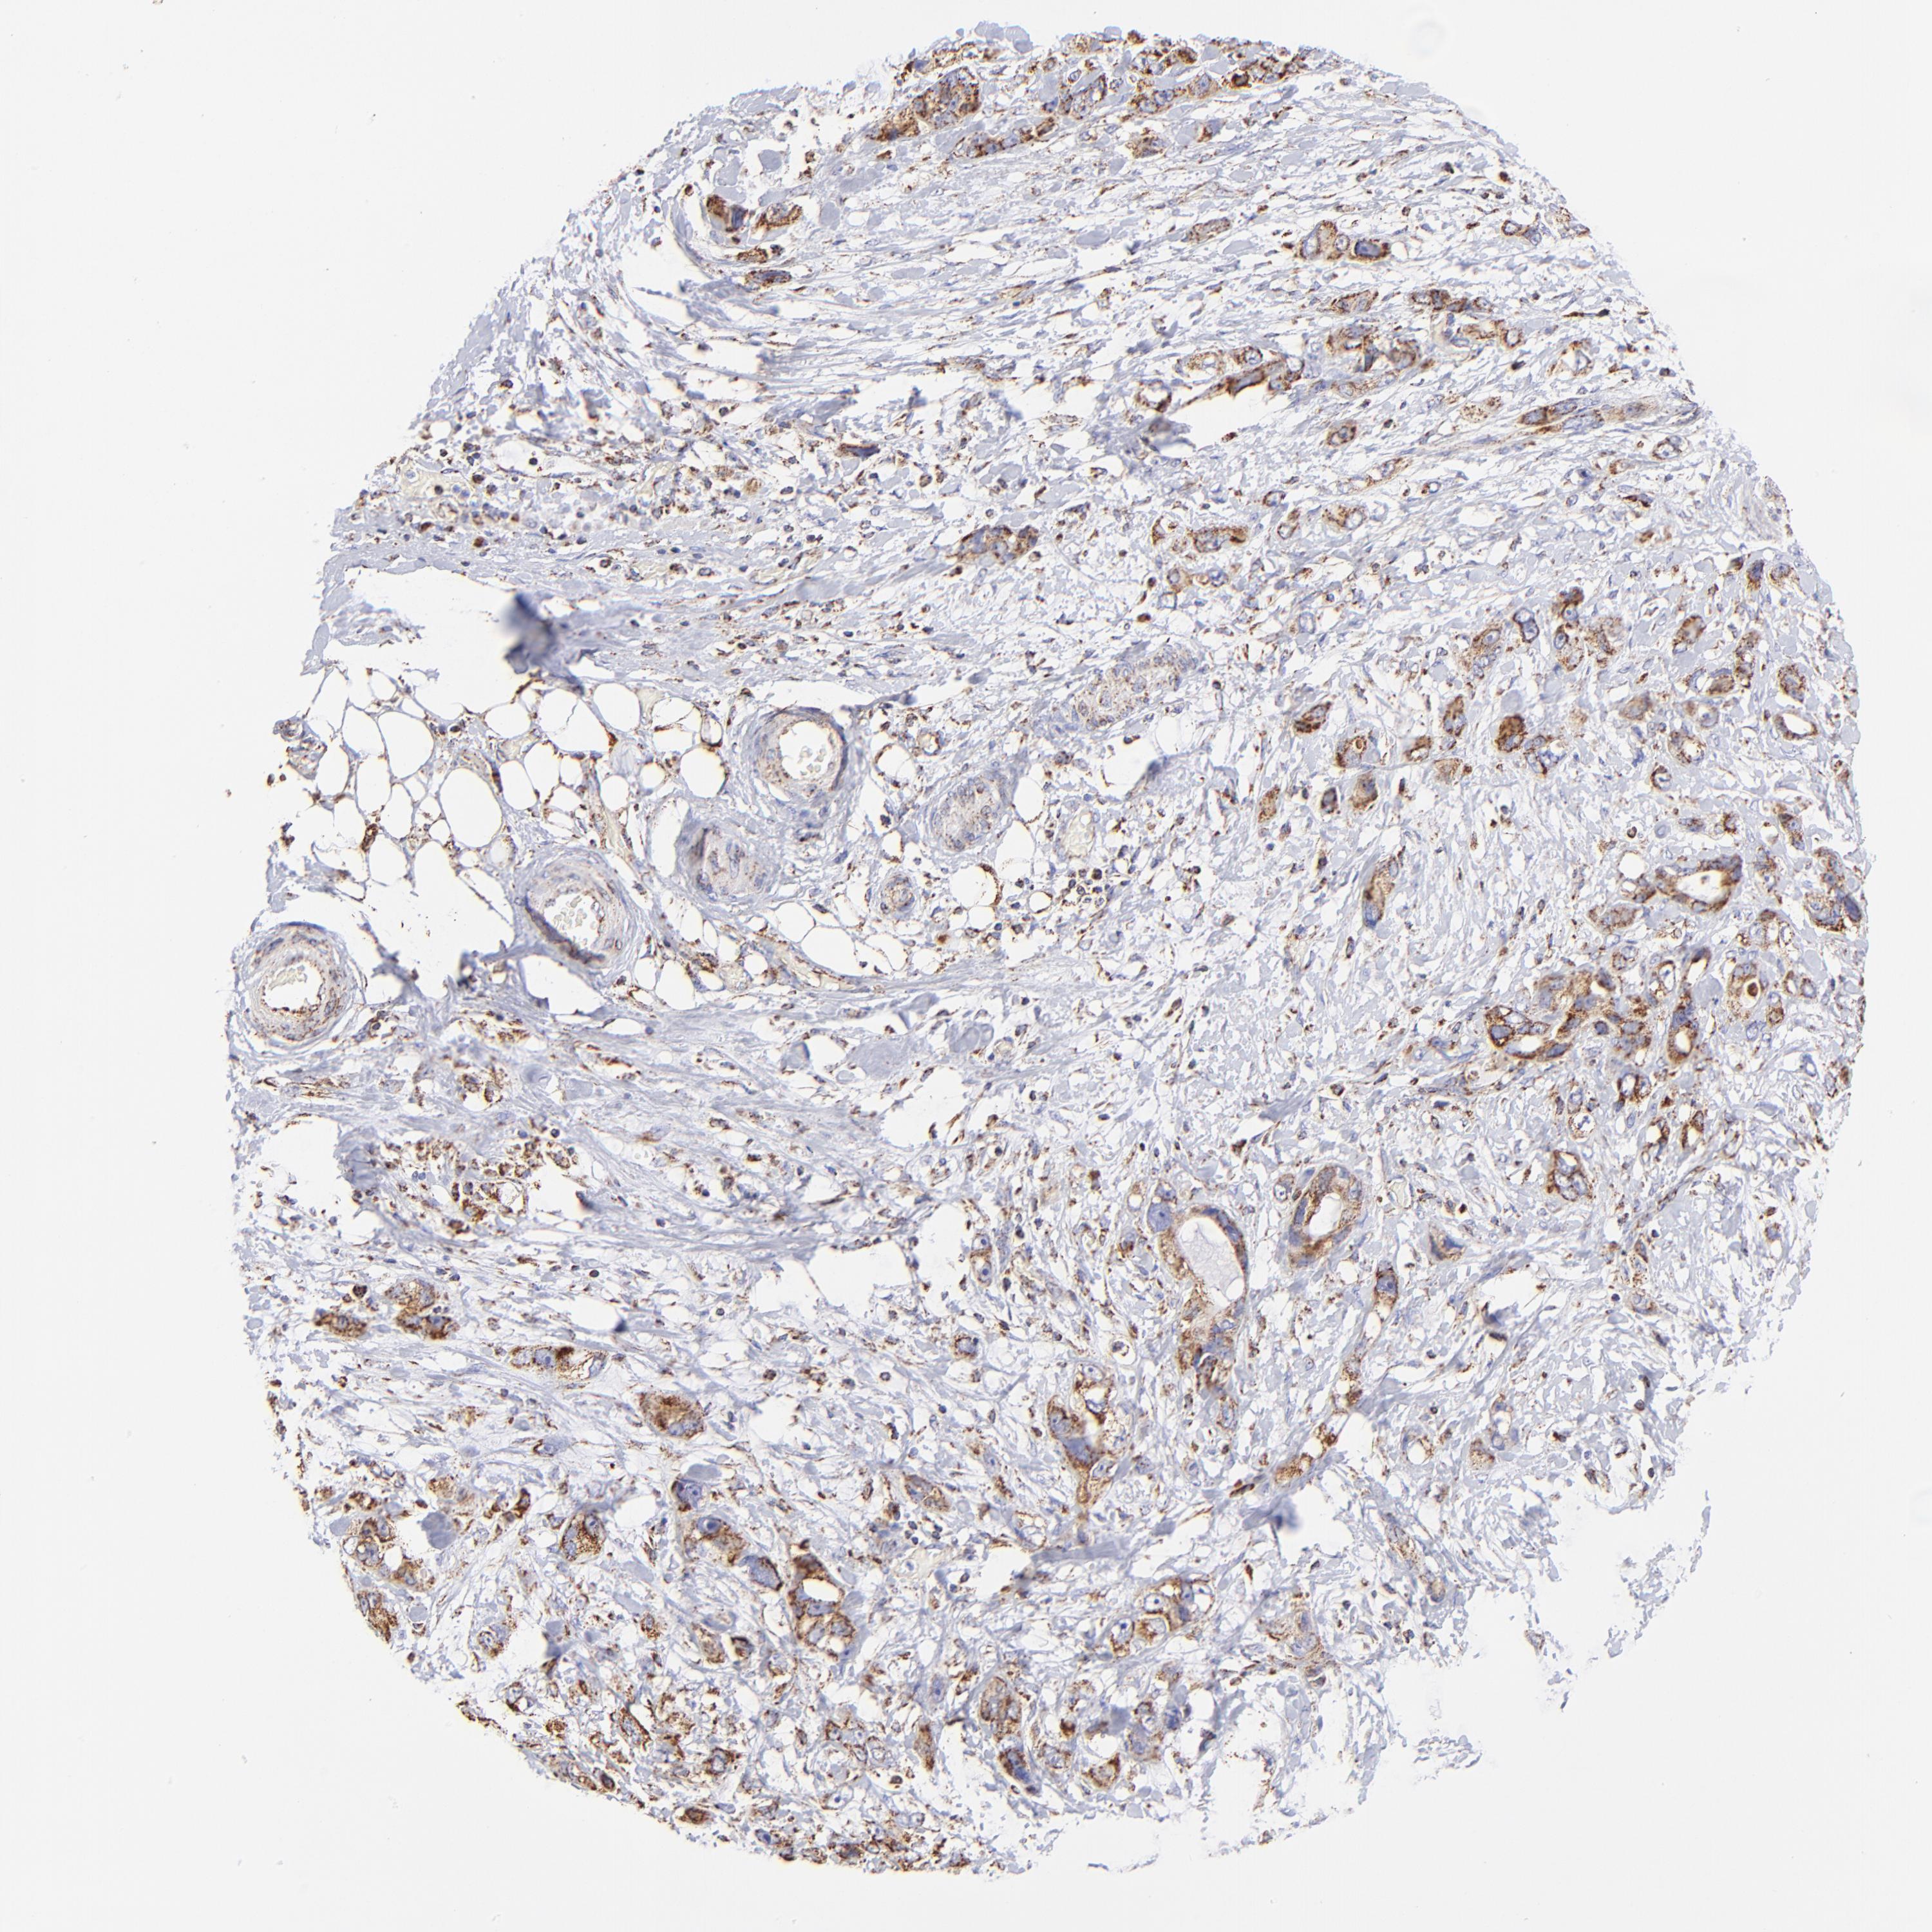

STOMACH CANCER - Protein expressioni

A mouse-over function shows sample information and annotation data. Click on an image to view it in a full screen mode. Samples can be filtered based on level of antibody staining by selecting one or several of the following categories: high, medium, low and not detected. The assay and annotation is described here.

Note that samples used for immunohistochemistry by the Human Protein Atlas do not correspond to samples in the TCGA dataset.

Antibody stainingi

Antibody staining in the annotated cell types in the current human tissue is reported as not detected, low, medium, or high, based on conventional immunohistochemistry profiling in selected tissues. This score is based on the combination of the staining intensity and fraction of stained cells.

Each image is clickable and will lead to virtual microscopy that enables deeper exploration of all samples and also displays staining intensity scores, fraction scores and subcellular localization as well as patient and tissue information for each sample.

Antibody HPA002907

Antibody HPA005835

Staining

High

Medium

Low

Not detected

Intensity

Strong

Moderate

Weak

Negative

Quantity

>75%

75%-25%

<25%

None

Location

Nuclear

Cytoplasmic/membranous

Cytoplasmic/membranous,nuclear

Adenocarcinoma, NOS

Adenocarcinoma, High grade